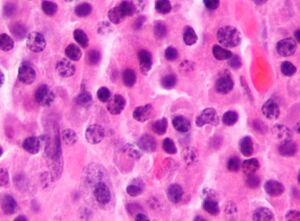

Bone marrow aspirate showing the histologic correlate of multiple myeloma under the microscope. H&E stain.

Plasmacytoma. H&E stain.